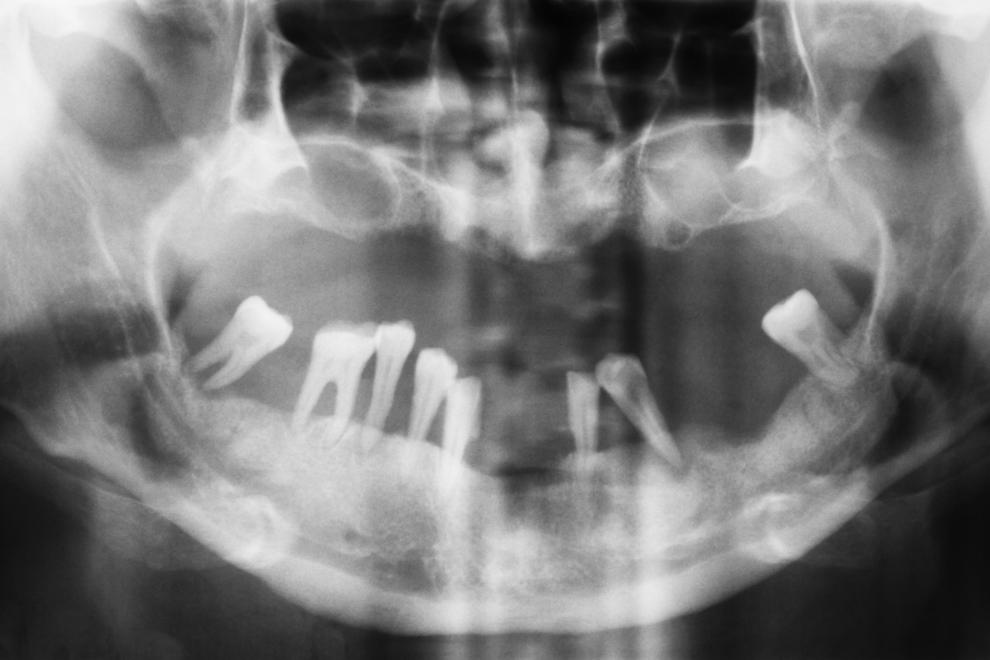

Para que un implante dental tenga éxito, la calidad del implante es tan importante como la del tejido óseo del maxilar o la mandíbula donde se integra. Sin una buena superficie de agarre, es muy difícil que el implante se mantenga en la boca del paciente por mucho tiempo: los odontólogos estiman que la zona de hueso que sustente a un implante debe tener como mínimo unos 10 mm de altura y unos 5 mm de espesor.

regeneración ósea, regeneración ósea sobre implantes

Los pacientes que han pasado muchos años edéntulos (sin dientes), suelen tener las pérdidas de hueso más significativas, y en estos casos, casi siempre es necesario uno de estos tratamientos de regeneración ósea previo a la colocación del implante.

Las personas de edad avanzada, con osteoporosis, enfermedad periodontal y/o que fuman tabaco (que afecta a la vascularización de la zona y provoca que la calidad del hueso sea menor), suelen ser los pacientes que más habitualmente necesitan de estas técnicas antes de hacerse un implante dental.